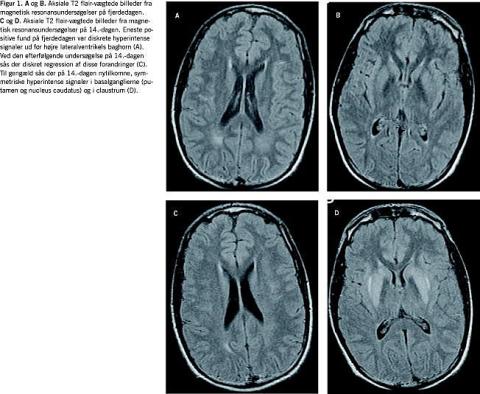

Efter to døgn var patienten cerebralt klar, men svarede stadig med latenstid. En magnetisk resonans (MR)-skanning fire dage efter indlæggelsen viste diskrete uspecifikke forandringer i den hvide substans ud for højre lateralventrikels baghorn (Figur 1 A+B).

Ti dage efter indlæggelsen var patienten motorisk urolig, dysartrisk, grædende, savlende, hypotensiv, havde sitrende trækninger i ansigtet og synkebesvær. Dosis af glukokortikoid var da 20 mg × 2 dagligt og P-Na var 140 mM. Resultaterne af et elektroencefalogram var foreneligt med diffus encefalopati, og patienten blev overflyttet til neurologisk regi på mistanke om ODS. Her fandt man påvirkning af kranienerverne VII, IX, X og XII samt ekstrapyramidal påvirkning med rigiditet, bradykinesi, amimisk ansigt og ændret kropsholdning. Der var ingen pyramidebanesymptomer. En MR-skanning 14 dage efter indlæggelsen viste symmetriske forandringer i basalganglierne, hvilket er foreneligt med ekstrapontin myelinolyse (EPM) (Figur 1 C+D). Forandringerne ud for baghornet var uændrede. Adrenomyeloneuropati, Wilsons sygdom og neurolues blev udelukket. Patienten blev behandlet med antiparkinsonmedicin med effekt på de ekstrapyramidale symptomer og blev efter genoptræning på Hammel Neurocenter udskrevet efter eget ønske 35 dage efter indlæggelsen. Ved udskrivelsen persisterede der kun let monoton tale, en højresidig primær hviletremor og en moderat afficeret diadokokinese.